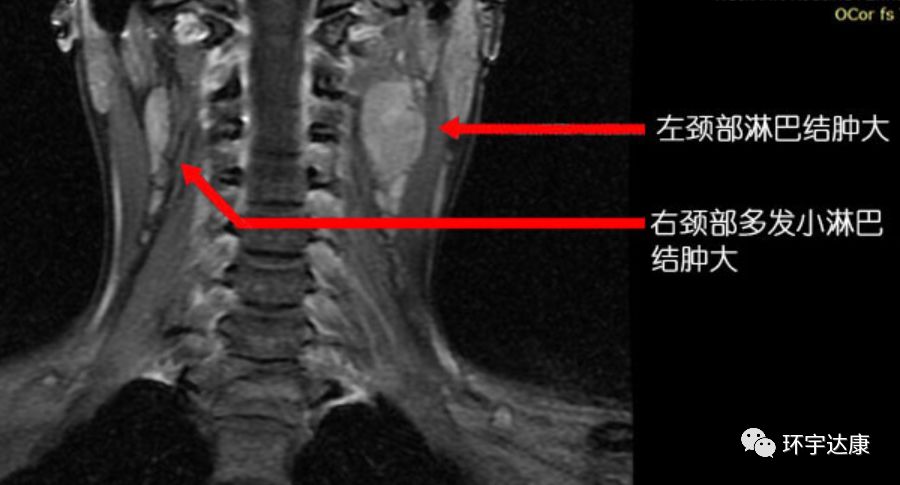

广东的吴女士在2013年7月出现左耳听力下降及左上颈明显肿大淋巴结,本以为是炎症,结果去医院检查后才被确诊为:非角化性癌,分化较差,鼻咽腔肿瘤侵润咽旁和颅底。双侧淋巴结转移。分期为:T3N1M0。

经过多西他赛+铂类化疗联合放疗后,病灶都有了明显的缩小。

不幸的是,2015年2月,复查结果显示,左侧鼻腔壁肿瘤局部复发。因为之前已经接受过了放疗,所以复发后吴女士可选的治疗方案很少。

再经过会诊后,吴女士了解到质子可以治疗复发的肿瘤,于是,吴女士选择了去国外接受质子质子治疗。

治疗期间,吴女士唾液分泌、皮肤、甲状腺无显著影响。治疗后MRI显示鼻咽左侧壁的局部复发已经明显缩小。两个月后吴女士开始正常上班。目前随访,病情处于稳定状态。